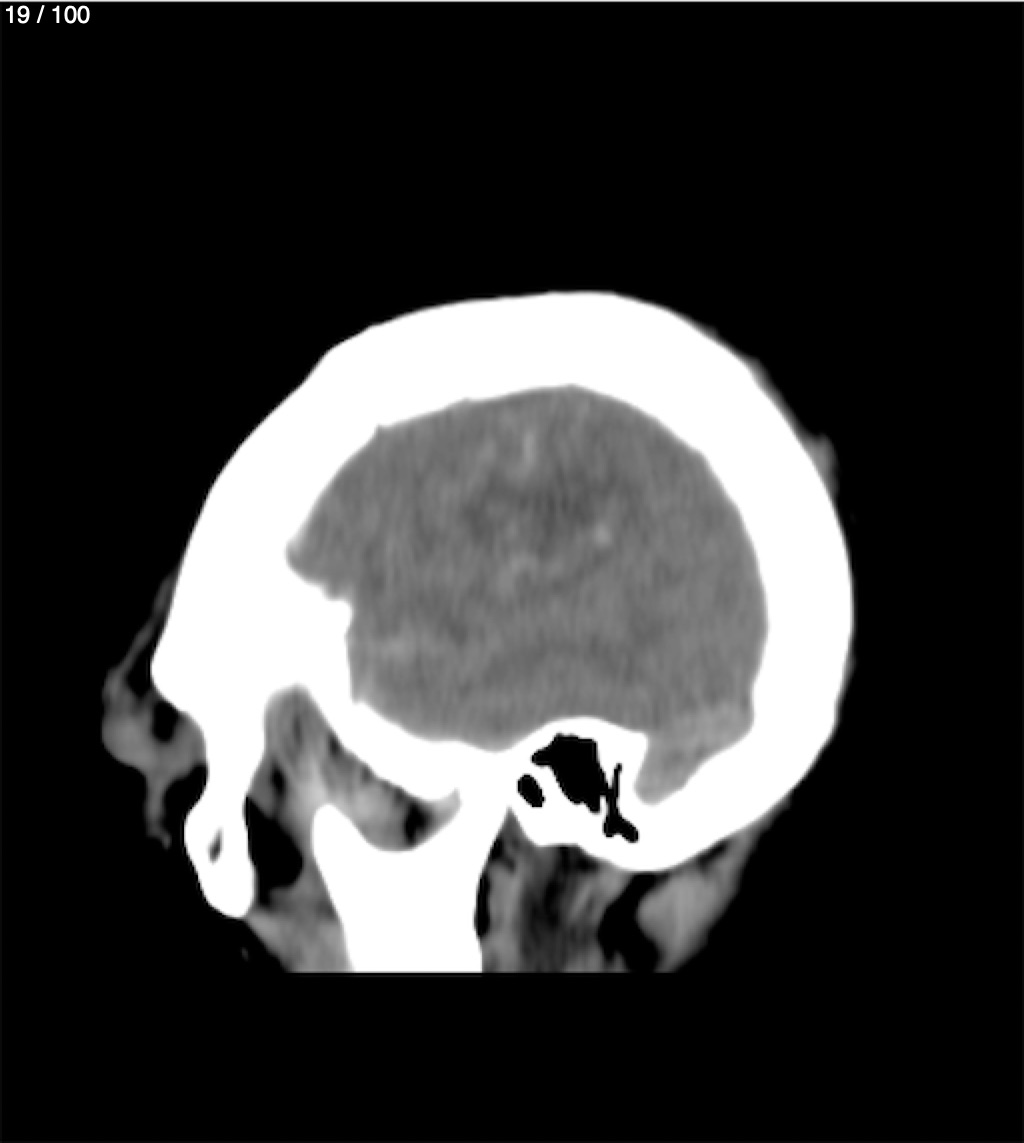

Maria Lopez Aguilar 78A - E+1 Tc Craneo